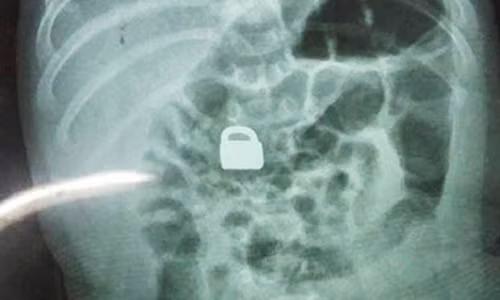

| Ổ khoá trong bụng bé 2 tháng tuổi. |

Người mẹ cho biết, chị thấy chiếc khóa mất tích nên đã hỏi con trai lớn và rất sốc cậu bé khai đã cho em ăn. Ngay lập tức, gia đình đưa bé 2 tháng tuổi tới bệnh viện kiểm tra. Các bác sỹ vô cùng ngạc nhiên khi thấy chiếc phát hiện ổ khoá trong bụng bé 2 tháng tuổi.

Do chiếc ổ khóa có kích thước khá nhỏ, chỉ 1,5 x 0,9 cm, to hơn móng tay người lớn một chút, nên các bác sỹ quyết định không mổ lấy dị vật mà để bé tự đào thải. Năm ngày sau đó, chiếc khóa đã được bài tiết ra ngoài. Kiểm tra y tế cũng xác nhận em bé sơ sinh có ổ khóa trong bụng trên không gặp vấn đề gì về sức khỏe.